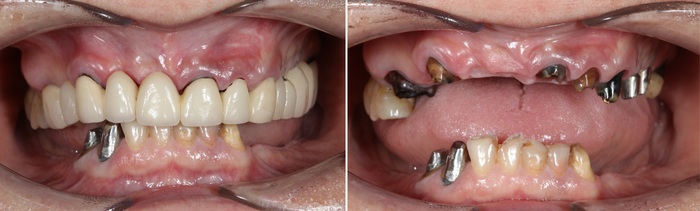

Девушка достаточно трепетно относится к зубам. Как мы видим, она активно занималась их лечением и восстановлением.

Но время неумолимо и беспощадно. Срок службы пломб, коронок и мостов подошел к концу. Кроме того, что полностью испортились свои зубы, так еще и в области установленных ранее имплантатов начались необратимые процессы.

Ниже панорамный снимок зубов пациентки

Вот на кой хер при такой ширине альвеолярной части установили средневековый пластиночный имплантат, остается для меня загадкой.

Итак, после того как были учтены результаты диагностики, консультация ортопеда и (что немаловажно) пожелания пациента (!), было принято решение об удалении всех зубов на верхней и нижней челюсти, в том числе установленных ранее имплантатов. Кроме пластиночного. Его я оставил на десерт.

Если вы думаете, что пациентка ушла из клиники без зубов, то вы ошибаетесь. Перед удалением в обязательном порядке ортопед снимает слепки челюстей. Далее техник изготавливает полные съемные протезы в лаборатории.

Пациентка с протезом, установленным сразу после удаления зубов и имплантатов.

Уже секс, согласны? С ним она будет ходить до момента его замены на постоянную конструкцию.

По прошествии двух месяцев после удаления можно приступать к имплантации.

На верхней челюсти были установлены шесть имплантатов и проведена операция по наращиванию костной ткани – синус-лифтинг (с обеих сторон). Через 2 недели установлены 8 имплантатов на нижней челюсти.

Спустя четыре месяца были установлены формирователи десны на верхней (снимок слева) и нижней (снимок справа) челюстях.